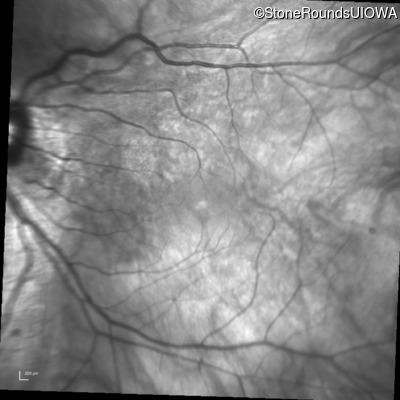

Infrared Fundus Photograph - Left - 20/25 +2

Exemplar